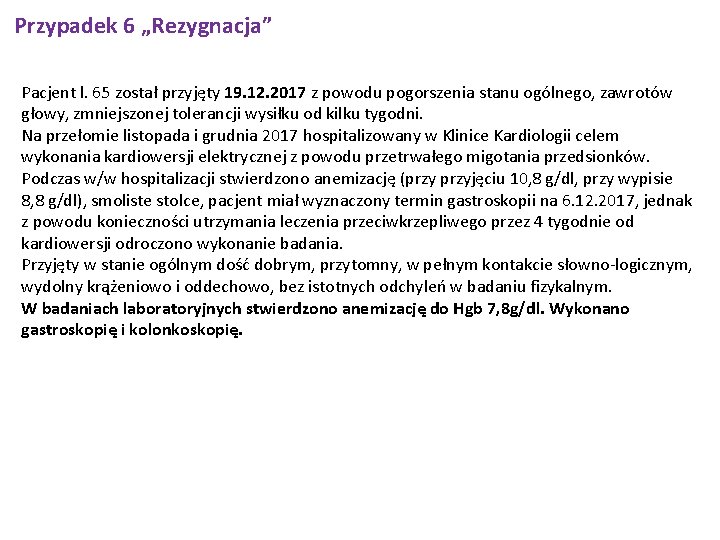

Przypadek 6 „Rezygnacja” Pacjent l. 65 został przyjęty 19. 12. 2017 z powodu pogorszenia stanu ogólnego, zawrotów głowy, zmniejszonej tolerancji wysiłku od kilku tygodni. Na przełomie listopada i grudnia 2017 hospitalizowany w Klinice Kardiologii celem wykonania kardiowersji elektrycznej z powodu przetrwałego migotania przedsionków. Podczas w/w hospitalizacji stwierdzono anemizację (przyjęciu 10, 8 g/dl, przy wypisie 8, 8 g/dl), smoliste stolce, pacjent miał wyznaczony termin gastroskopii na 6. 12. 2017, jednak z powodu konieczności utrzymania leczenia przeciwkrzepliwego przez 4 tygodnie od kardiowersji odroczono wykonanie badania. Przyjęty w stanie ogólnym dość dobrym, przytomny, w pełnym kontakcie słowno-logicznym, wydolny krążeniowo i oddechowo, bez istotnych odchyleń w badaniu fizykalnym. W badaniach laboratoryjnych stwierdzono anemizację do Hgb 7, 8 g/dl. Wykonano gastroskopię i kolonkoskopię.

Przypadek 6 „Rezygnacja” CKD Usługi RTG 19 -12 -2017 Zdjęcie klatki piersiowej w 2 projekcjach - Wynik Rtg kl. piersiowej pa, bok-Pola płucne bez zmian ogniskowych. Sylwetka serca niepowiększona. Cienie klipsów na lewym zarysie serca. Aorta piersiowa wydłużona, ze zwapnieniami w łuku. Zarys kopuł przepony gładki. Kąty przeponowo-żebrowe wolne. Stan po sternotomii. Zmiany zwyrodnieniowe odcinka piersiowego kręgosłupa.